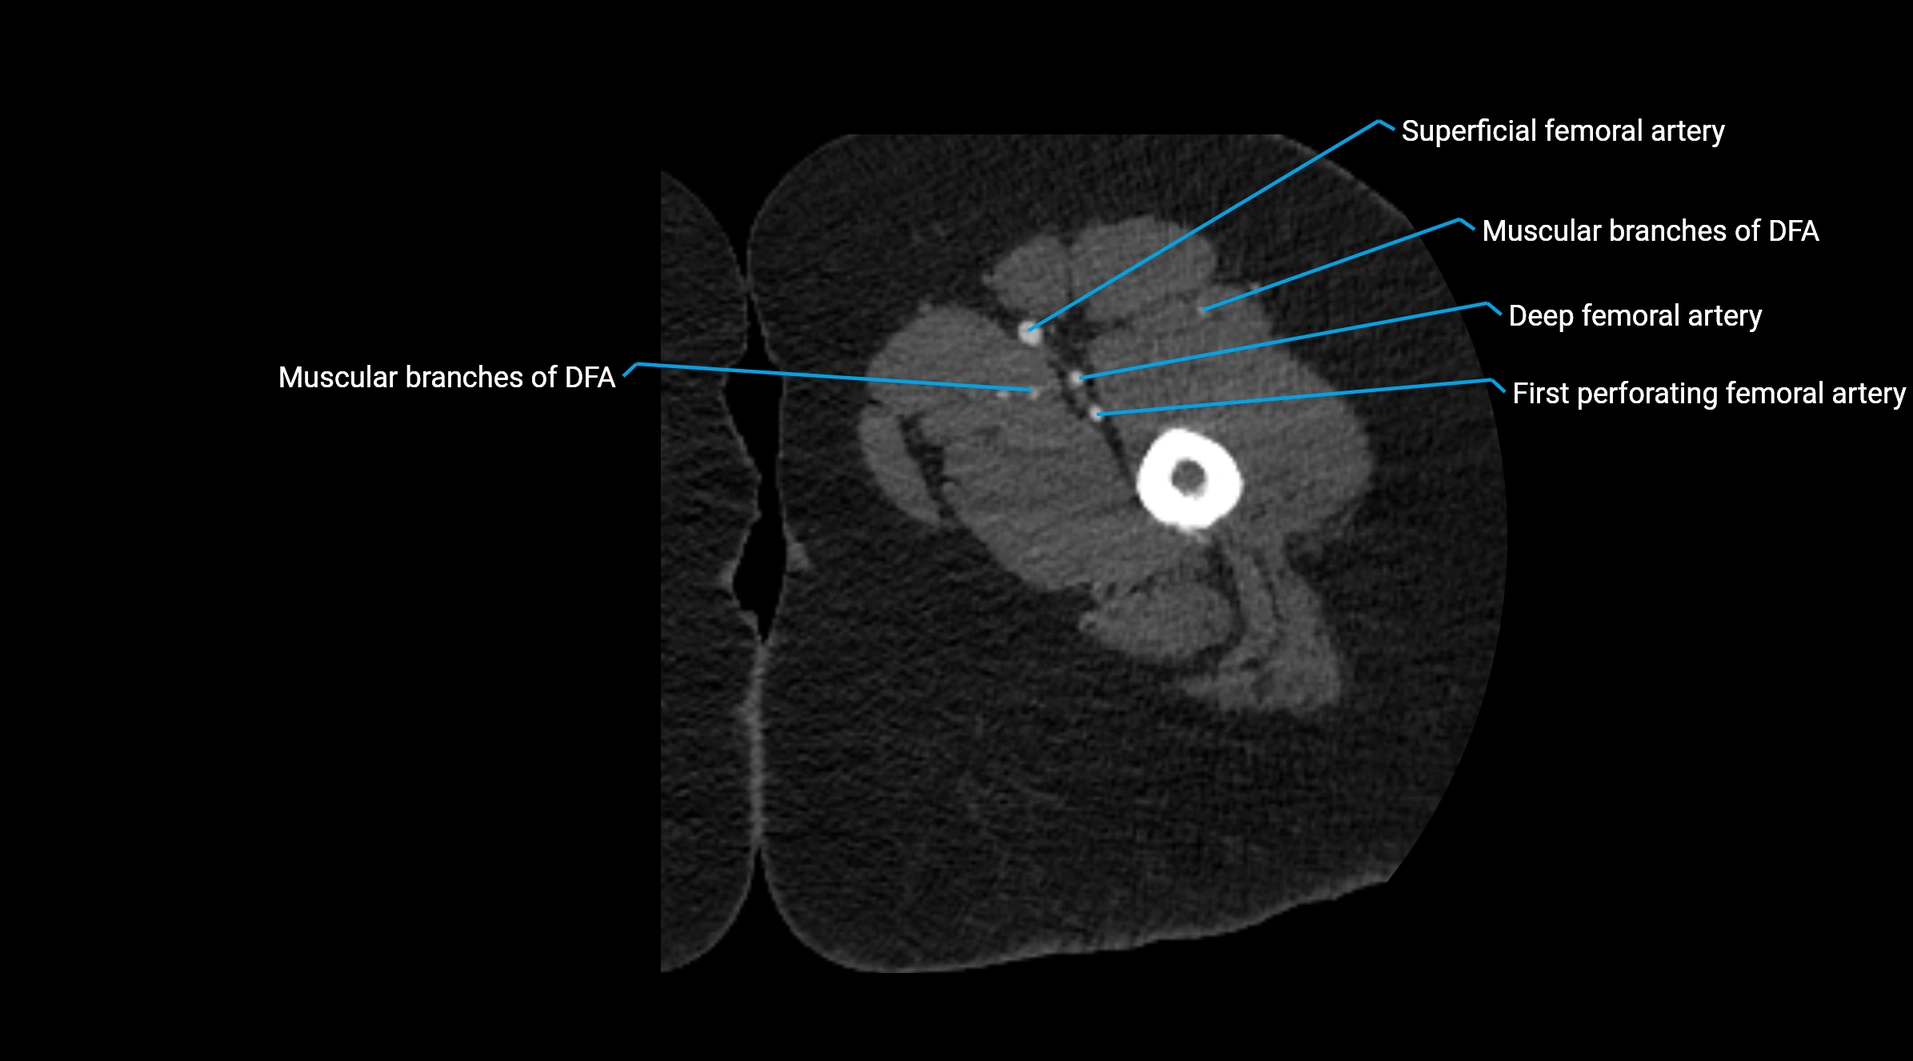

CT images

image